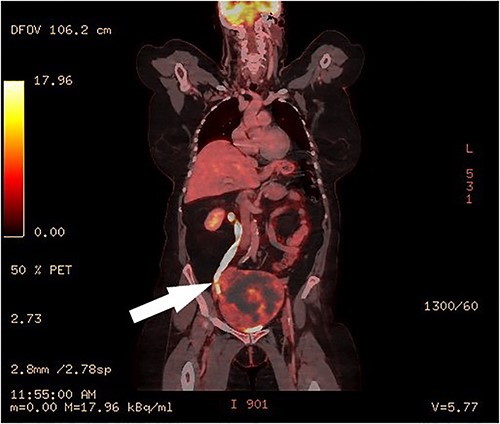

Clinical vaginal examination revealed a circumferentially distended uterine cervix. Vaginal ultrasound scan and magnetic resonance imaging (MRI) showed a strongly vascularized mass that completely involved the whole cervix. The mass measured 118 × 117 × 124 mm and showed irregular echogenicity with signs of diffuse necrosis centrally, suspicious for sarcomatous degeneration (Fig. 1). Positron emission tomography-computed tomography (PET-CT) showed a heterogenous and irregular hypermetabolic uterus, suspected for malignancy (Fig. 2). There were no signs of distant metastases nor lymphadenopathy. PET-CT also showed a distended ureter with hydroureteronephrosis on the right side, suspicious of compression/obstruction of the right ureter (Figs 2–4).

PET-CT, coronal image of a dilated right ureter with stenosis at the pelvic mass.